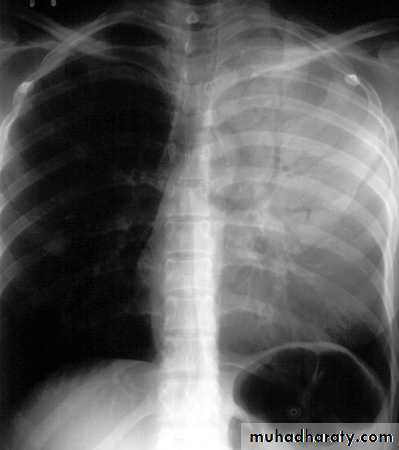

Tension pneumothorax.

On a posteroanterior chest x-ray (A), the left hemithorax is very dark or lucent because the left lung has collapsed completely (white arrows).

The tension pneumothorax can be identified because the mediastinal contents, including the heart, are shifted toward the right, and the left hemidiaphragm is flattened and depressed. A computed tomography scan done on a different patient with a tension pneumothorax (B) shows a completely collapsed right lung (arrows) and shift of the mediastinal contents to the left.